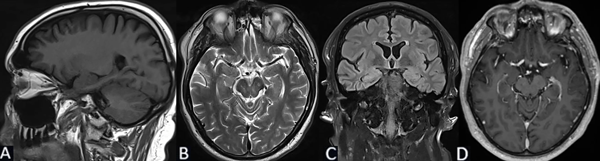

Se solicita RM cerebral con contraste, de cortes finos, donde se evidencia en secuencia T1 imagen de aspecto globuloso en la región hipocampo amigdalina paramediana derecha, ligeramente hipointensa de 2.7 x 2.5 x 1.3 cm. En T2 se comporta como hiperintensa, sin efecto de masa, sin edema perilesional. No presenta cambios posteriores a la inyección del medio de contraste (Figura 2).

Figura 2. Caso 2: RM de cerebro. A) Secuencia T1. Corte sagital. B) Secuencia T2. Corte axial. C) Secuencia T2 “TIRM Dark Fluid”. Corte coronal. D) Secuencia T1 con contraste. Corte axial.